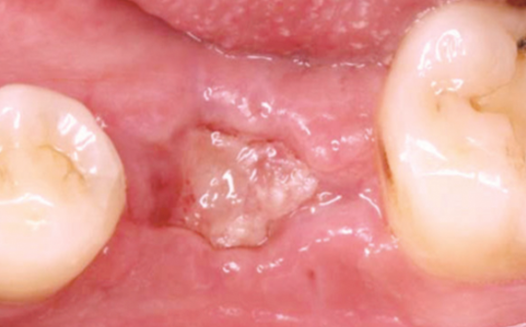

발치 부위의 잇몸이 주저앉는 것을

독자적인 노하우로 예방한 모습

상악동거상술의 출혈, 붓기, 수술시간 등이 걱정될 환자분을 위하여 강남새로치과는 독자적인 방식의 잇몸뼈 재생술로 상악거상술을 진행하여 출혈, 붓기 뿐 아니라 수술시간의 부담을 효과적으로 줄여드립니다.